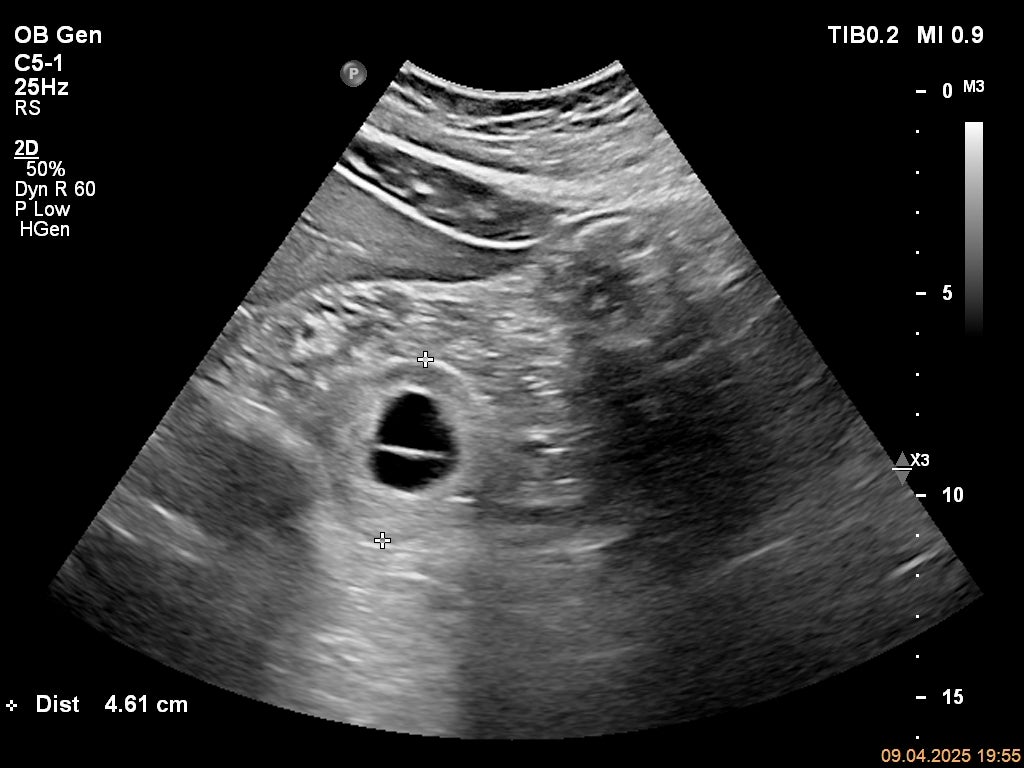

ECOGRAFIE PĂRȚI MOI: regiune fesieră stângă (imaginea 2): corespunzător masei palpate se evidențiază o voluminoasă formațiune solidă, lobulată, infiltrativă cu dezvoltare din planul osos, cu dimensiuni de 3.8/5/5.8 cm, volum 59.5cmc; masa este inomogenă, bine vascularizată (Doppler color), cu multiple calcificări (ring-artefacte prezente în Doppler color).